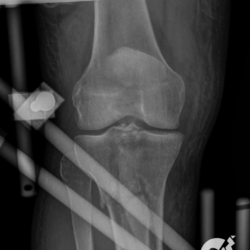

Fratura da patela com importante desvio e fratura cominutiva do 1/3 proximal da tíbia comprometendo a eminência intercondiliana.